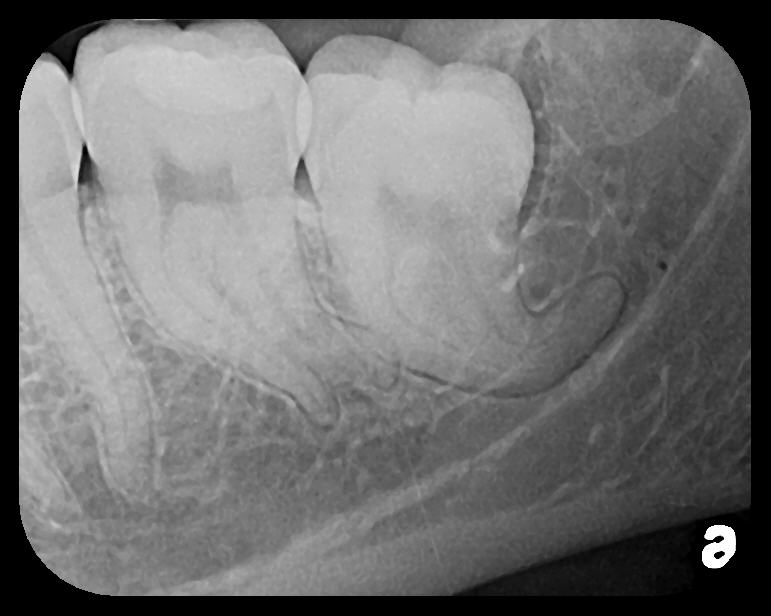

Fig 13. An easily placed pediatric

PSP no. 2 size right side BW radiograph shows the presence of second

molars and the normal pattern of eruption of the bicuspids in this patient,

age 7.

Figure 13

Fig 14. Bilateral BW PSP radiographs on this 8-year-old patient

demonstrate agenesis of bicuspid Nos. 20 and 29. Primary tooth Nos. K

and T must be evaluated for long-term retention.

Figure 14